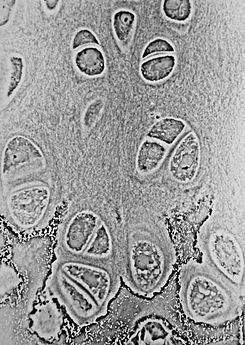

El cartílago hialino está cubierto externamente por una membrana fibrosa, llamada pericondrio, excepto en los extremos articulares de los huesos y también donde se encuentra directamente debajo de la piel, es decir, las orejas y la nariz. Esta membrana contiene vasos que le proporcionan nutrición al cartílago. Si se observa una delgada capa bajo el microscopio, se encontrará que está formado por células con forma redondeada o sin puntas, en grupos de dos o más en una matriz biológica granular o casi homogénea. Al microscopio óptico no se observa red fibrilar en la matriz extracelular, pero sin embargo al utilizar luz polarizada pueden visualizarse redes de fibrillas. Este efecto óptico es debido a que el índice de refracción de las fibrillas es similar al de la matriz en las que se encuentran inmersas. La matriz extracelular es una red 3D muy compleja. Las células se encuentran en las cavidades de la matriz, llamada lagunas del cartílago;en torno a estas la matriz está dispuesta en líneas concéntricas, como si se hubiera formado en porciones sucesivas alrededor de las células del cartílago. Esto constituye la llamada cápsula del espacio. Cada laguna está generalmente ocupada por una sola célula, pero durante la división de las células puede contener dos, cuatro u ocho células, lo que constituye un grupo isogénico o grupo de células isogénicas. El cartílago hialino también contiene condrocitos que son las células del cartílago que producen la matriz. La matriz hialina del cartílago se compone sobre todo de colágeno tipo II3 y sulfato de condroitina, los cuales también se encuentran en el cartílago elástico.